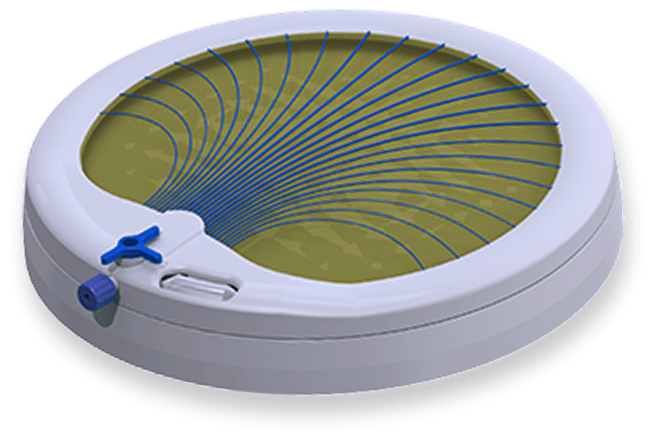

With ScleroTrainer®, you will be able to strengthen your skills and techniques while simulating the feel and effect of sclerotherapy on a person.